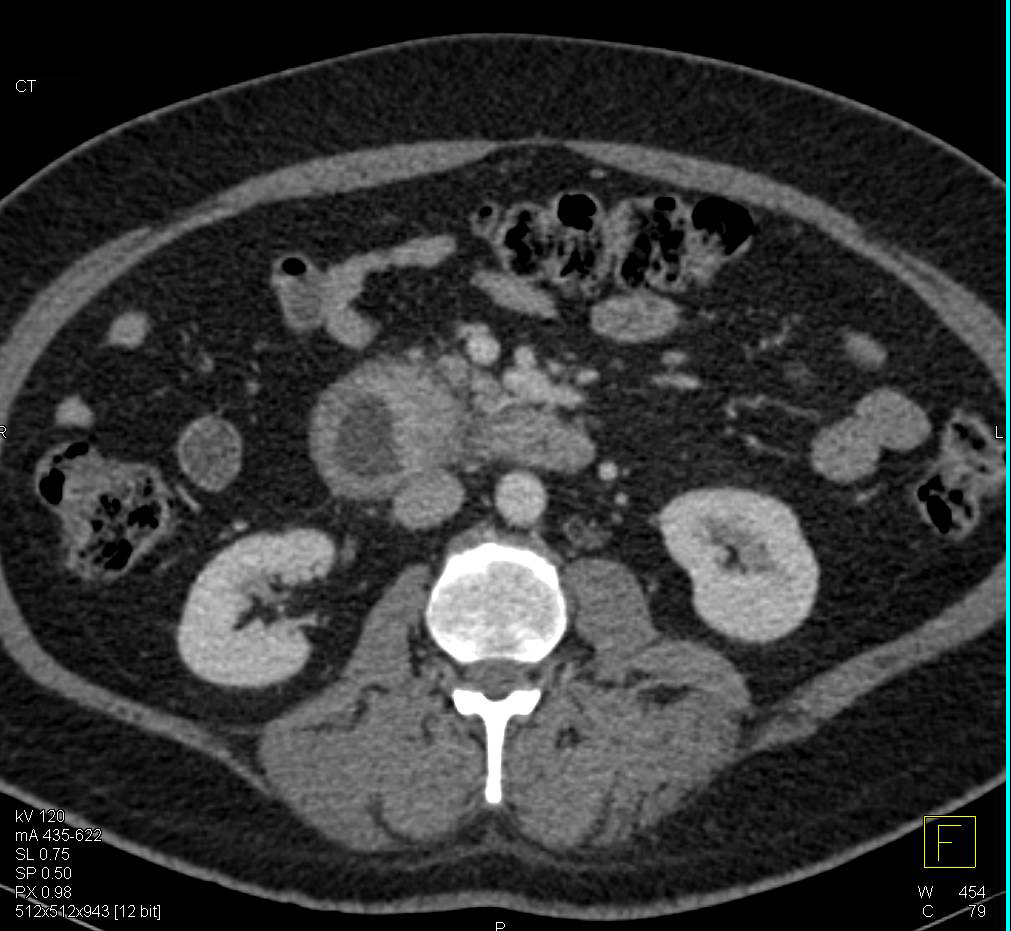

Serous Cystadenoma Tail of the Pancreas